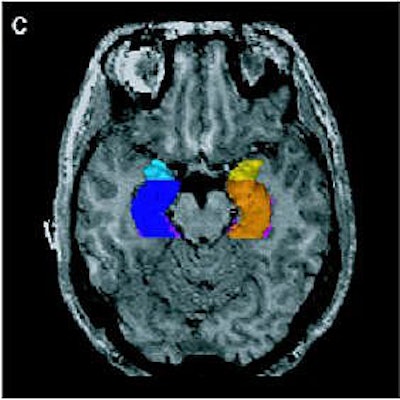

| Above, regions of interest (ROI) examined in MRI study of patients with first-episode schizophrenia or affective psychosis and normal comparison subjects. Top (A) is a 1.5-mm coronal slice of the temporal lobe; the ROI used to evaluate the temporal structures are outlines. The gray matter of the superior temporal gyrus is shown in red (subject left) and green (subject right); more medially, the amygdala-hippocampal complex is shown in orange (left) and blue (right) with the parahippocampal gyrus underneath in pink (left) and purple (right). Below, a left lateral view of a 3D reconstruction of the cortical surface with the anterior superior temporal gyrus (light pink) and posterior superior temporal gyrus (red). |

![]() |

| Same subject. Above and below, axial MRI is used to present top-down views of the 3D reconstruction of the amygdala-hippocampal complex and parahippocampal gyrus. All images: Figure 1, Hirayasu Y, Shenton ME, Salisbury DF, et al. "Lower Left Temporal Lobe MRI Volumes in Patients with First-Episode Schizophrenia Compared with Psychotic Patients With First-Episode Affective Disorder and Normal Subjects," (Am J Psychiatry 1998; 155:1384-1391). |